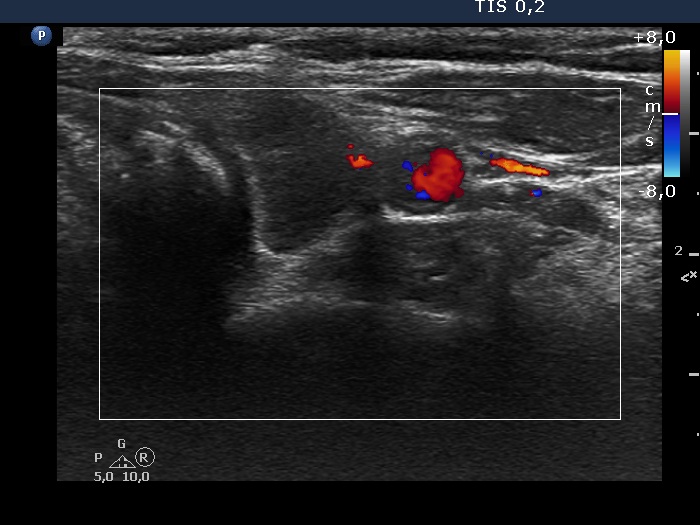

Second examination 3 years later (second, fourth and sixth rows of images):

Ultrasonography. Compared with the previous examination, both the number and the size of discrete lesions in the thyroid have increased.